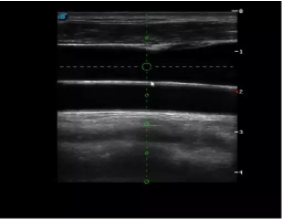

實時觀察穿刺針進(jìn)入血管的全過程,方便操作及較短的穿刺路徑,智能進(jìn)針尺寸提示,讓置管工作更加輕松,高效。

不同進(jìn)針路徑